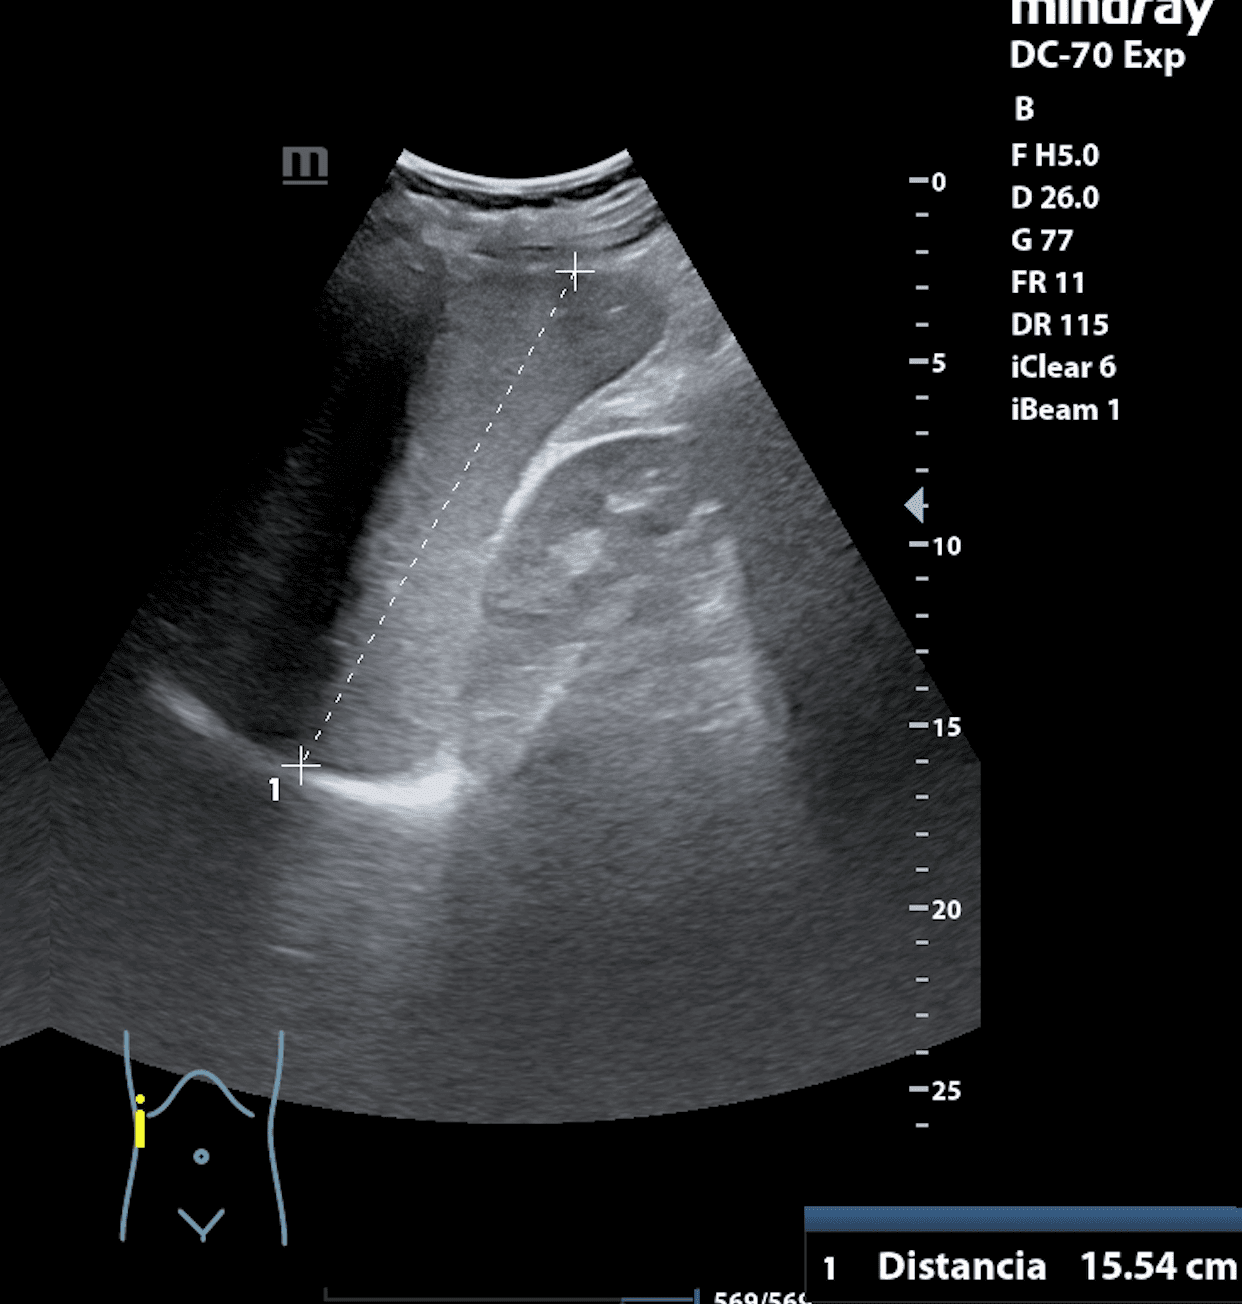

Hallazgos ecográficos

Hepatomegalia y esplenomegalia de 21,03 cm. Adenopatías retroperitoneales.